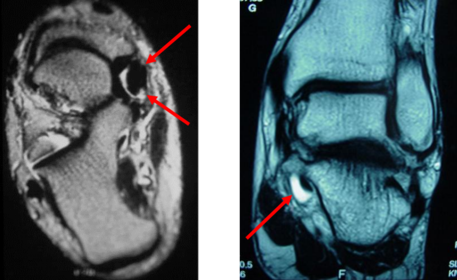

What does the red arrow show? What does the yellow arrow show? | Red arrow = fluid Yellow arrow = tendon tear |

What does the arrow indicate? | Fluid |

What do the arrows indicate? | Tenosynovitis |